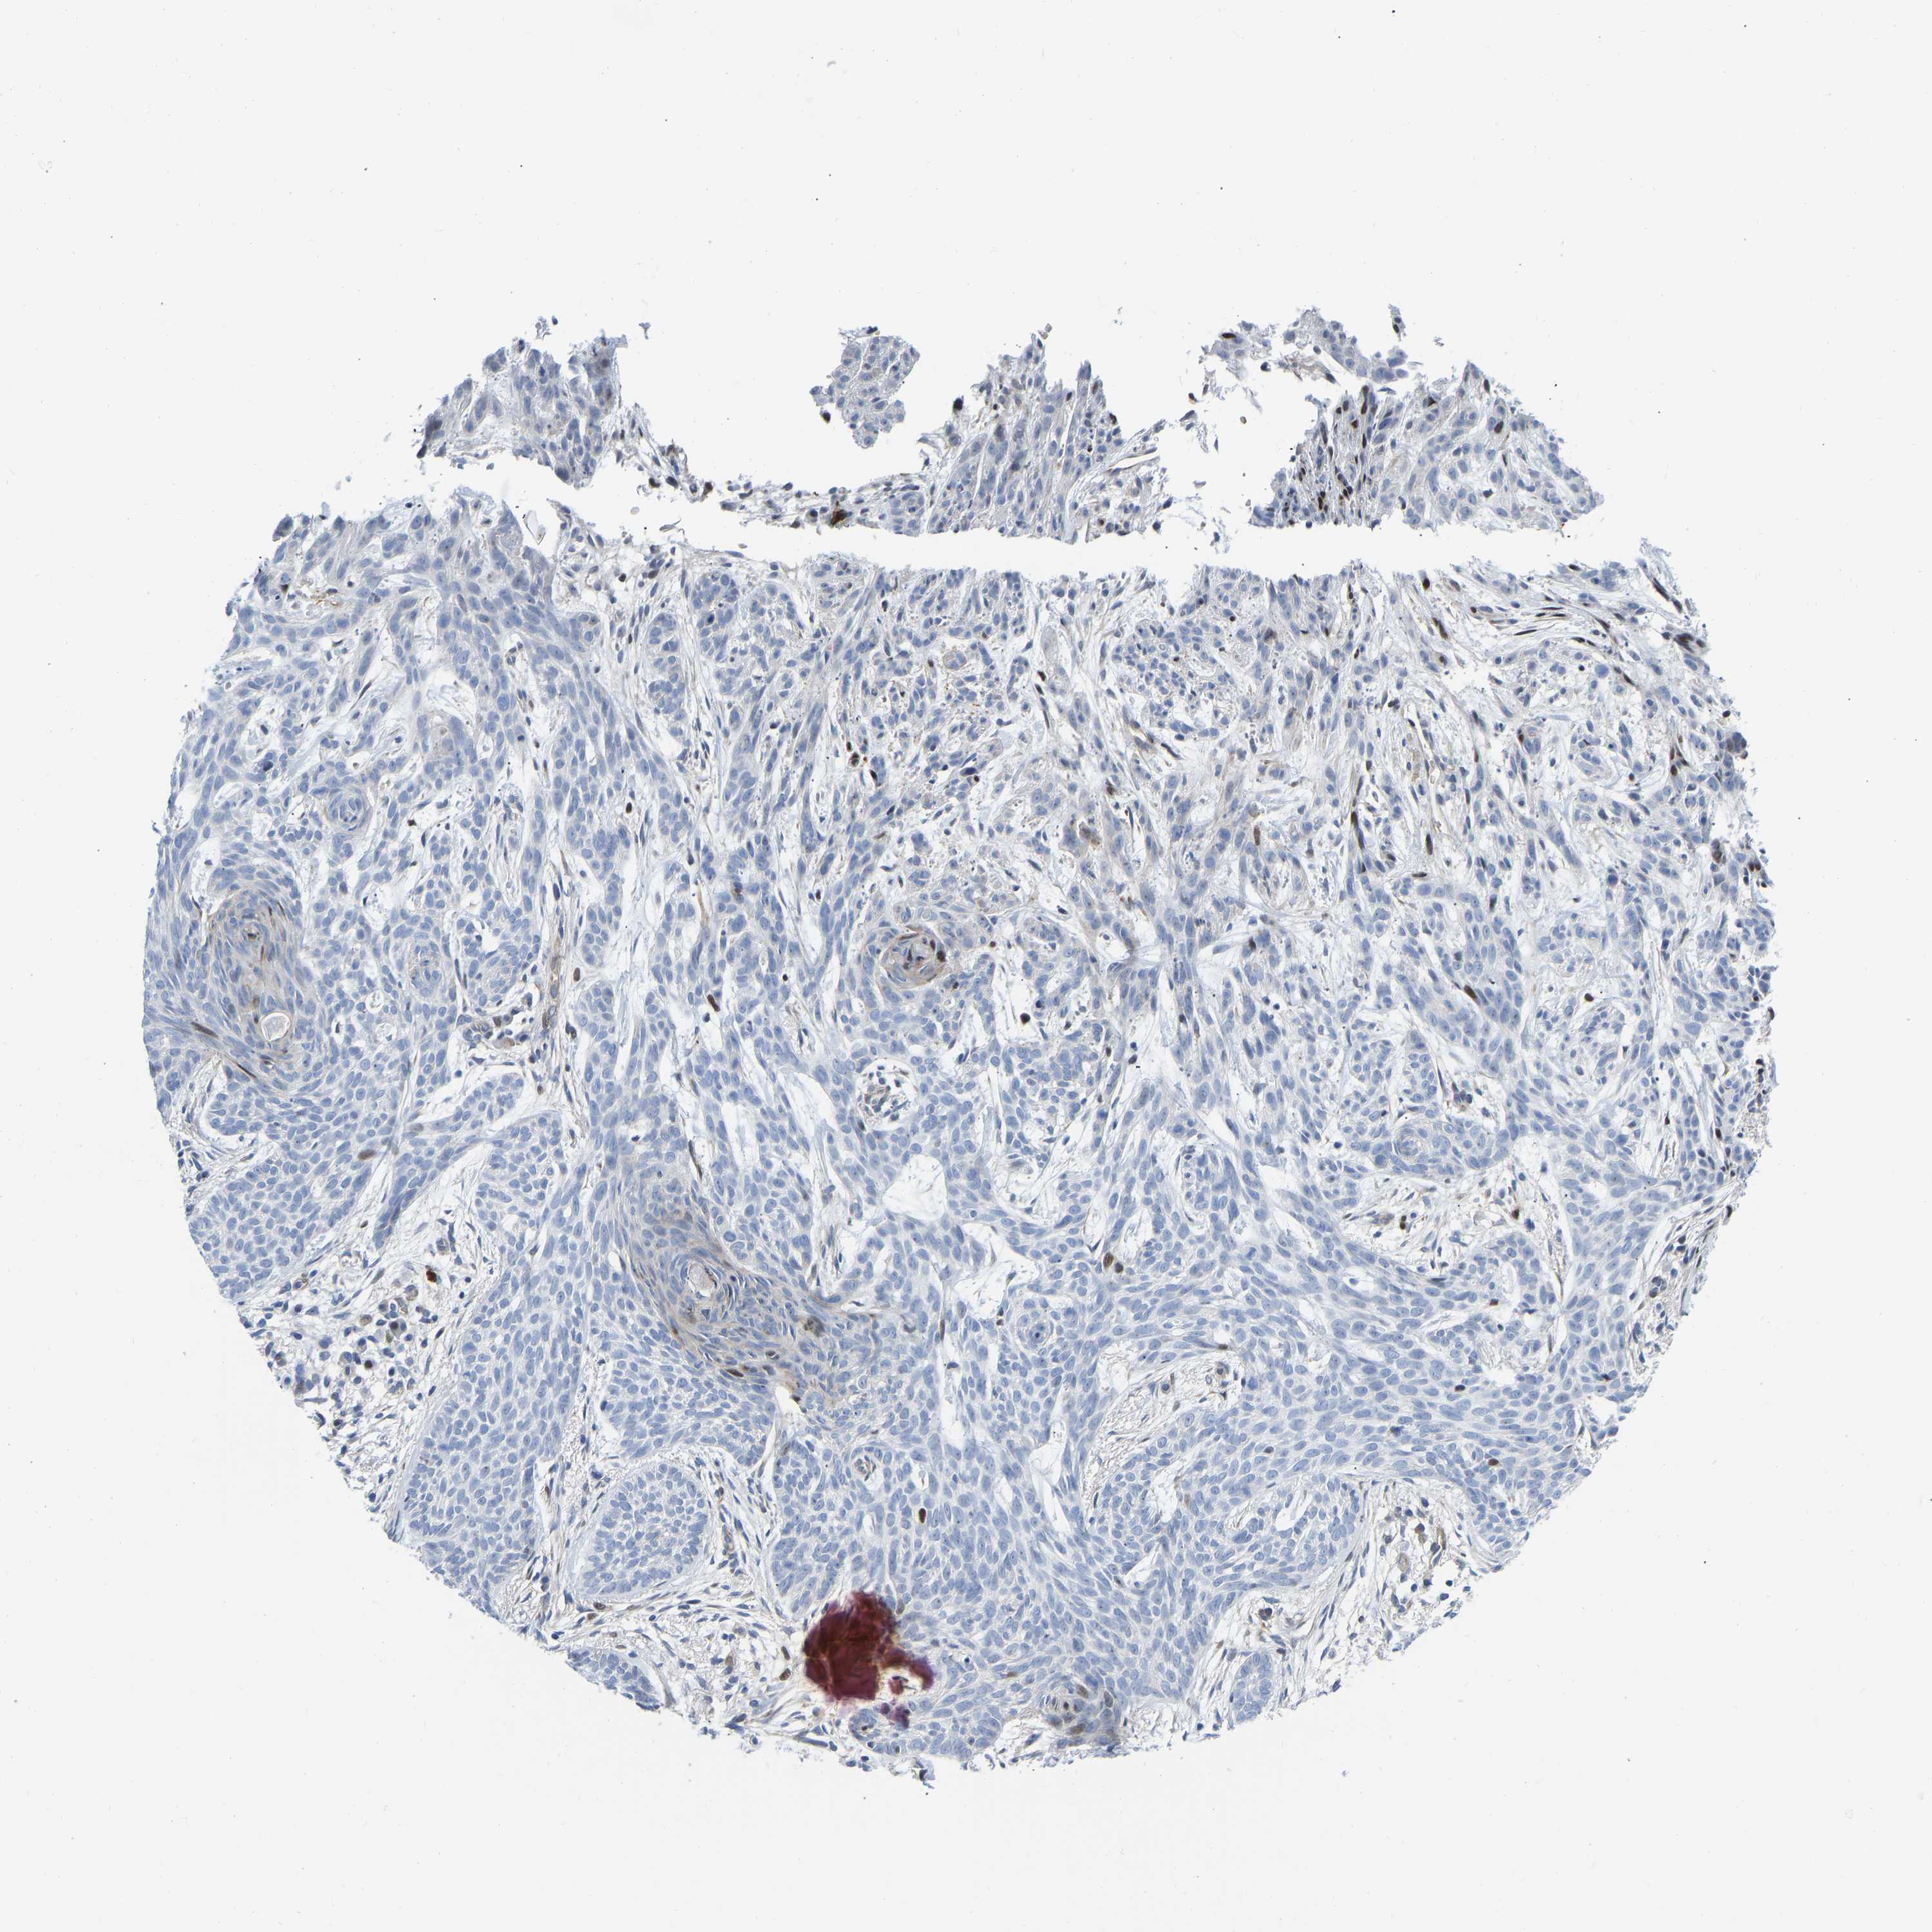

SKIN CANCER - Protein expressioni

A mouse-over function shows sample information and annotation data. Click on an image to view it in a full screen mode. Samples can be filtered based on level of antibody staining by selecting one or several of the following categories: high, medium, low and not detected. The assay and annotation is described here.

Antibody stainingi

Antibody staining in the annotated cell types in the current human tissue is reported as not detected, low, medium, or high, based on conventional immunohistochemistry profiling in selected tissues. This score is based on the combination of the staining intensity and fraction of stained cells.

Each image is clickable and will lead to virtual microscopy that enables deeper exploration of all samples and also displays staining intensity scores, fraction scores and subcellular localization as well as patient and tissue information for each sample.

Antibody HPA030991

Basal cell carcinoma